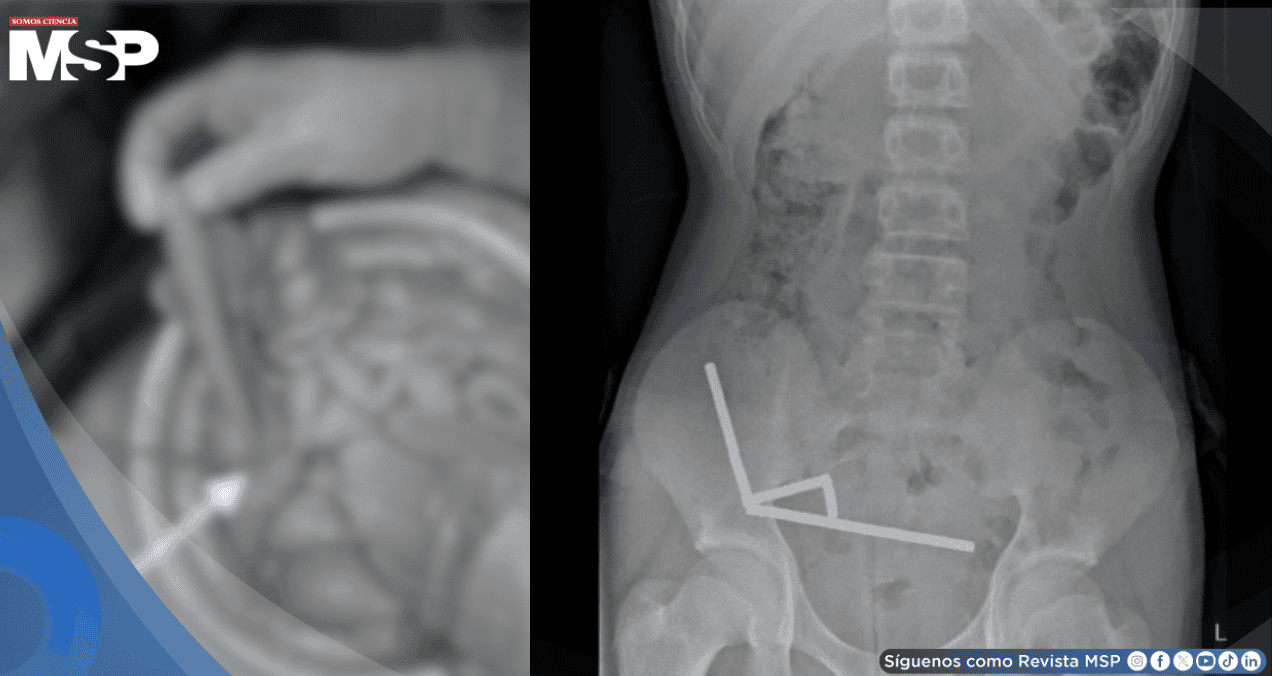

Los exámenes médicos revelaron que el joven había ingerido entre 80 y 100 imanes de neodimio de alta potencia una semana antes de su hospitalización.

Durante la intervención quirúrgica, los médicos descubrieron una situación crítica en el sistema digestivo del adolescente.

Los pequeños imanes, de apenas 5 x 2 milímetros cada uno, se habían unido para formar cuatro cadenas dentro de sus intestinos. Esta agrupación magnética causó graves daños al tejido intestinal, obligando a los cirujanos no solo a extraer los imanes, sino también a remover secciones completas del intestino que habían resultado irreparablemente afectadas por la presión constante de los imanes unidos.